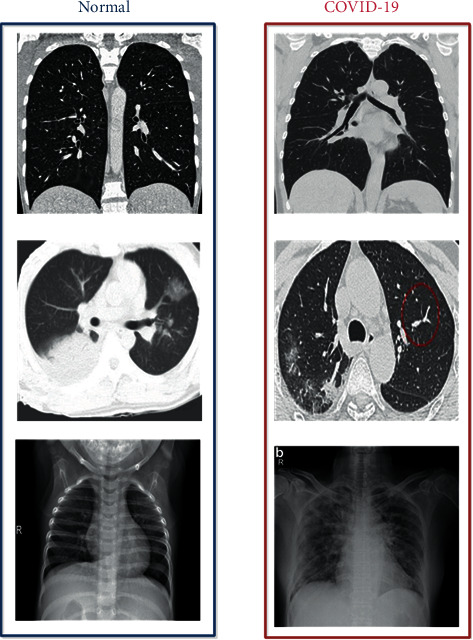

Our main goal here is to achieve good results in detecting COVID-19 cases. In this work, the datasets are gathered into two subsets, 80% for training and 20% for testing, including normal and COVID-19 cases. Figure 4 shows the CT and X-ray images.

Figure 4.

Example of X-ray and CT images of a normal patient and a COVID-19 patient.